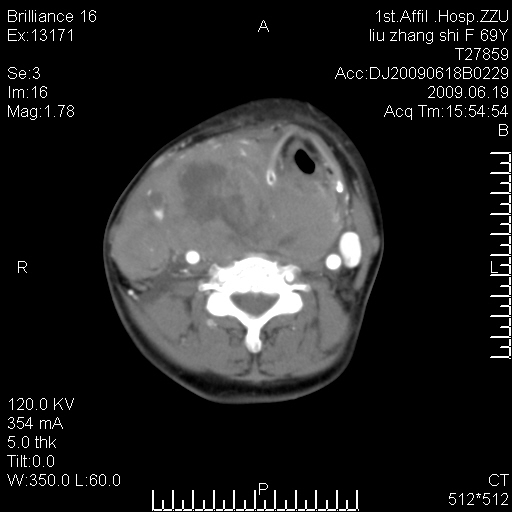

标题: CT26782:女,69岁,颈部占位,3天后公布病理结果。

【病理证实系列】女,69岁,颈部占位,有病理结果,3天后公布。(由于病例时间较久,临床资料不全,请网友见谅)本系列将有几百种常见、少见及罕见病例,均经病理证实。病例资料来自郑州大学第一附属医院。与网友共享,本人有空就发。

甲状腺癌并颈部淋巴结转移。感谢楼主的良苦用心,谢谢。

支持甲状腺癌广泛侵及周围结构并颈部淋巴结转移。

鉴别:淋巴瘤、恶性神经源性病变、恶性纤维组织细胞瘤。

病理结果:颈部非霍奇金淋巴瘤。